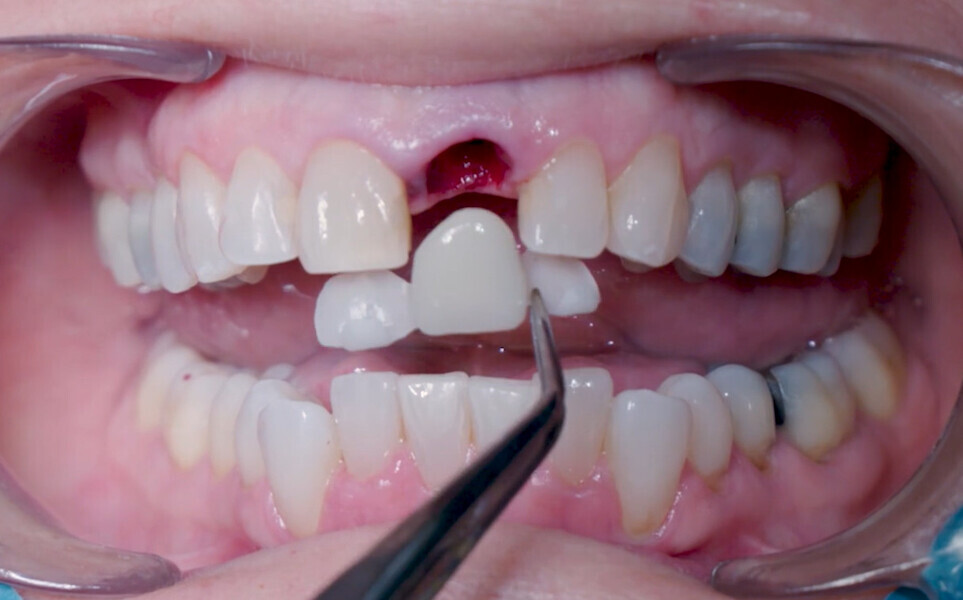

Fig. 22: Fitting assessment of provisional tooth shell.

Fig. 23: Fitting assessment of provisional tooth shell.